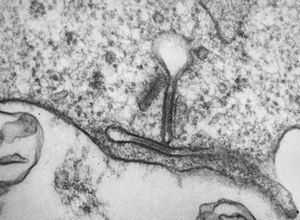

M,7m. | a formation of Birbeck granule(Langerhans granule, X-granule) - skin, histiocytosis X

M,7m. | Birbeck granules (Langerhans granules, X-granules) - skin, histiocytosis X